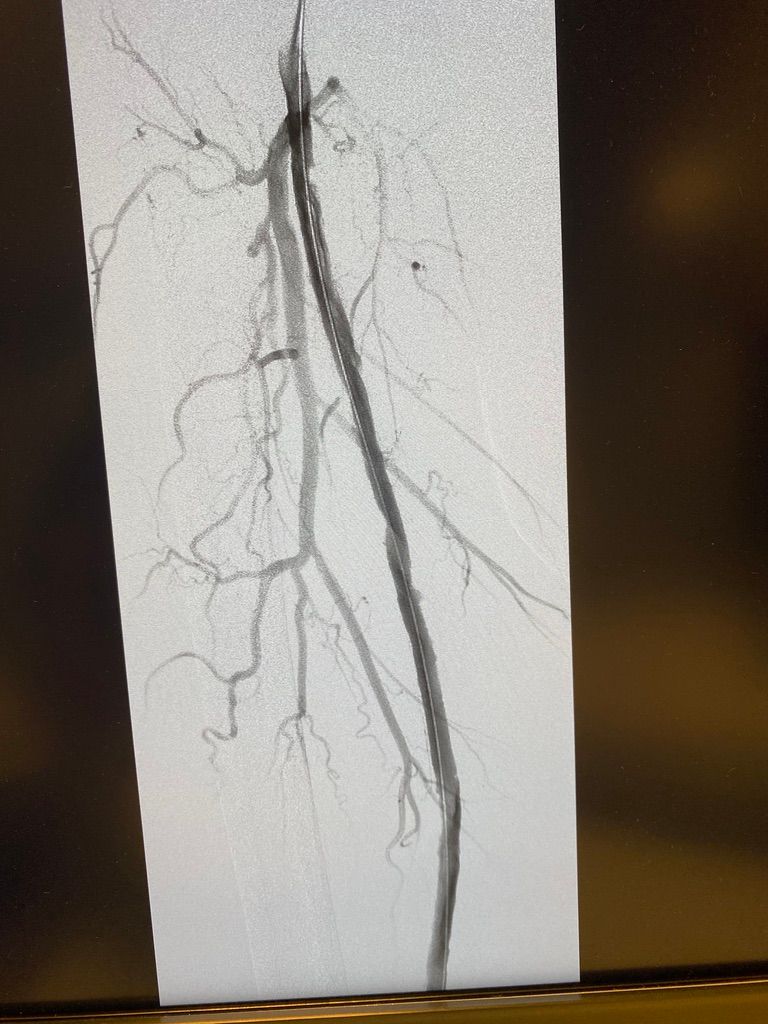

Dal 1997 al 2009 ha lavorato a tempo pieno presso Maria Cecilia Hospital di Cotignola come Cardiologo interventista eseguendo procedure interventistiche di PTCA sul distretto coronarico, carotideo, PTA del distretto iliaco-femorale, renale, e tibiale; Procedure percutanee di impianto di endoprotesi nel in aorta toracica e addominale, impianto percutaneo di valvole aortiche (TAVI), chiusura di Difetti interatriali e forami ovali.

VALUTAZIONE DI PROCEDURE INTERVENTISTICHE (vascolare, patologie delle carotidi, delle arterie iliacofemorali, arterie tibiali nel piede diabetico, aorta addominale e toracica) E CARDIOLOGICHE (angioplastiche coronariche, TAVI, chiusura di difetti interatriali e forami ovali pervi)